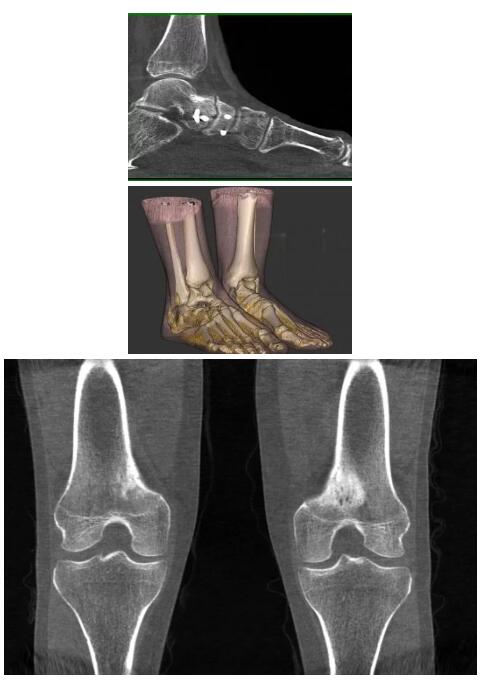

而患者站著做足部或者踝部做CT檢查還有個好處是,可以檢查患者在負重的情況下,骨關節(jié)的真實情況,而躺著做CT掃查時未必能看出來。負重CT掃查特別是對于受傷的運動員或者舞蹈員來說意義更大,能夠更準確地評估傷情,幫助他們盡早復原。

以上介紹的CT均來自國外同一家公司,這些CT均配置了可視化軟件,可以進行切片、3D重建以及大型CT附帶的所有典型的操作功能。

當然,這類充滿想象力的CT,國內(nèi)也有生產(chǎn)廠家在研究,比如賽諾威盛研發(fā)的InsitumCT Zero,可以很好的適應特殊的臨床應用場景,超大孔徑多種自由度組合,可實現(xiàn)水平和垂直等多種掃描模式。

對于急診外傷患者,它縮短了診斷到治療的路徑,避免移動患者帶來的二次損傷;復合手術(shù)室中,它可以讓醫(yī)生第一時間確認或調(diào)整手術(shù)方案,大大縮短手術(shù)時間;對于需要放療定位、質(zhì)子治療的患者,一站式的定位、治療服務能夠更加精準。

以下是這些“特立獨行”的CT所拍出來的圖像: